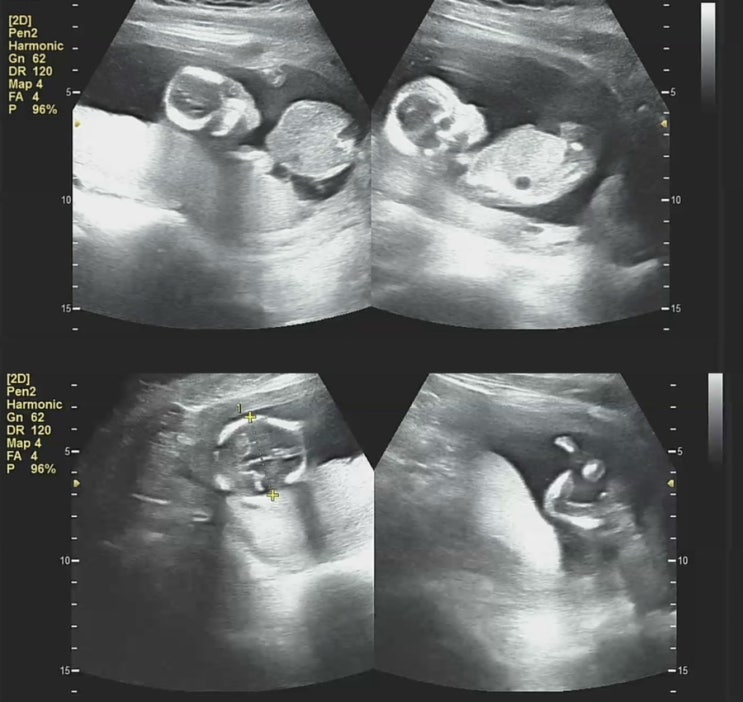

임밍아웃.. 내년4월에 만나자

갑작스러운 임신으로 혼란스러운 시간을 보내고 어느덧 16주차 1차 기형아검사 잘 통과했고 성별확인도 끝...